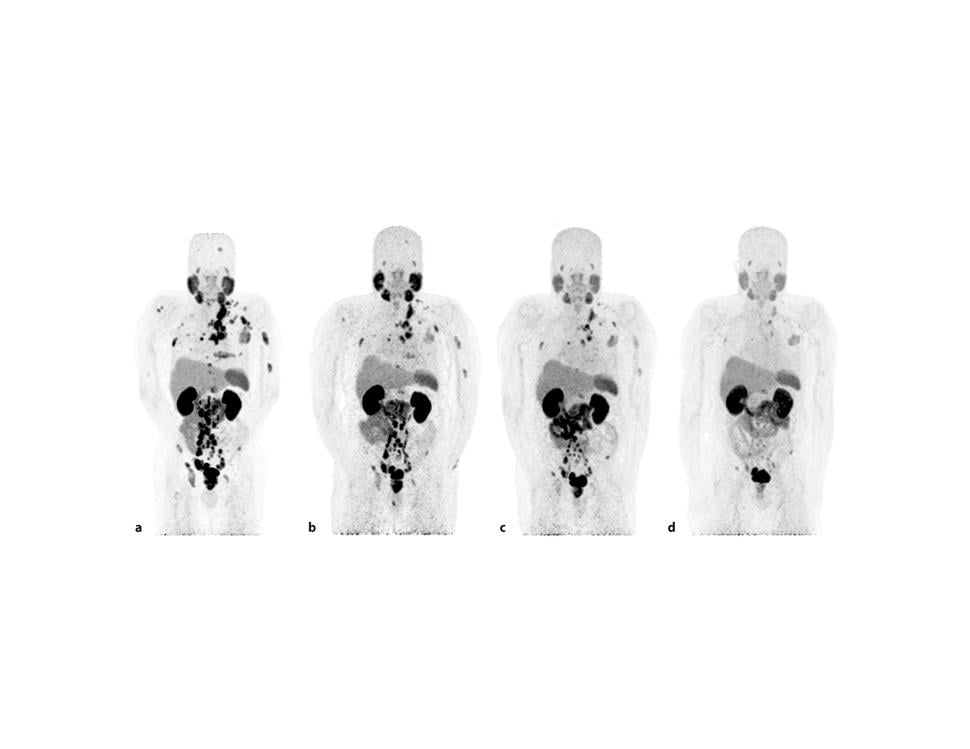

PSMA PET-CT